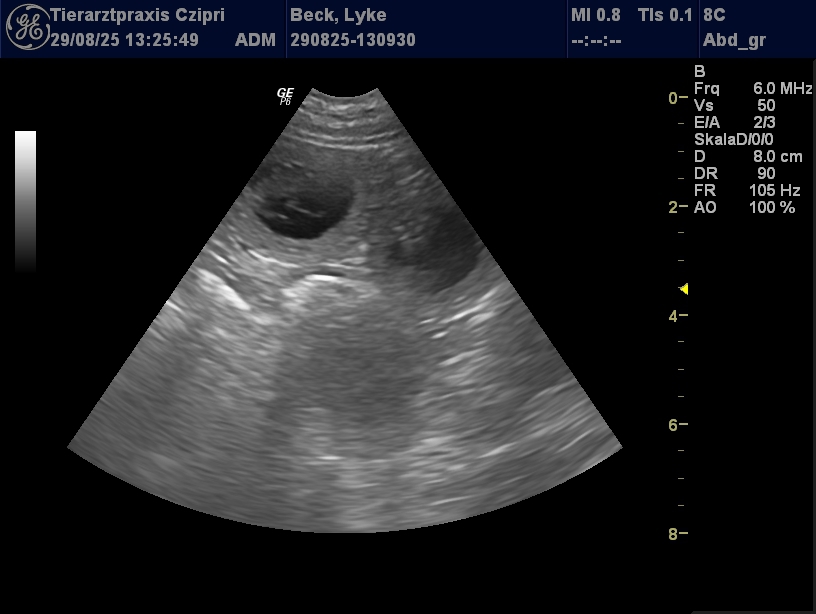

Wir freuen uns sehr! Der Ultraschall gestern hat gezeigt, dass Lykke Welpen haben wird und es sieht nach einem normel großen Wurf aus! :-)

Jetzt freuen wir uns auf eine hoffentlich wieder problemlose Trächtigkeit von Lykke und die Geburt Anfang Oktober.

Der errechnete Geburtstermin ist der 4. Oktober